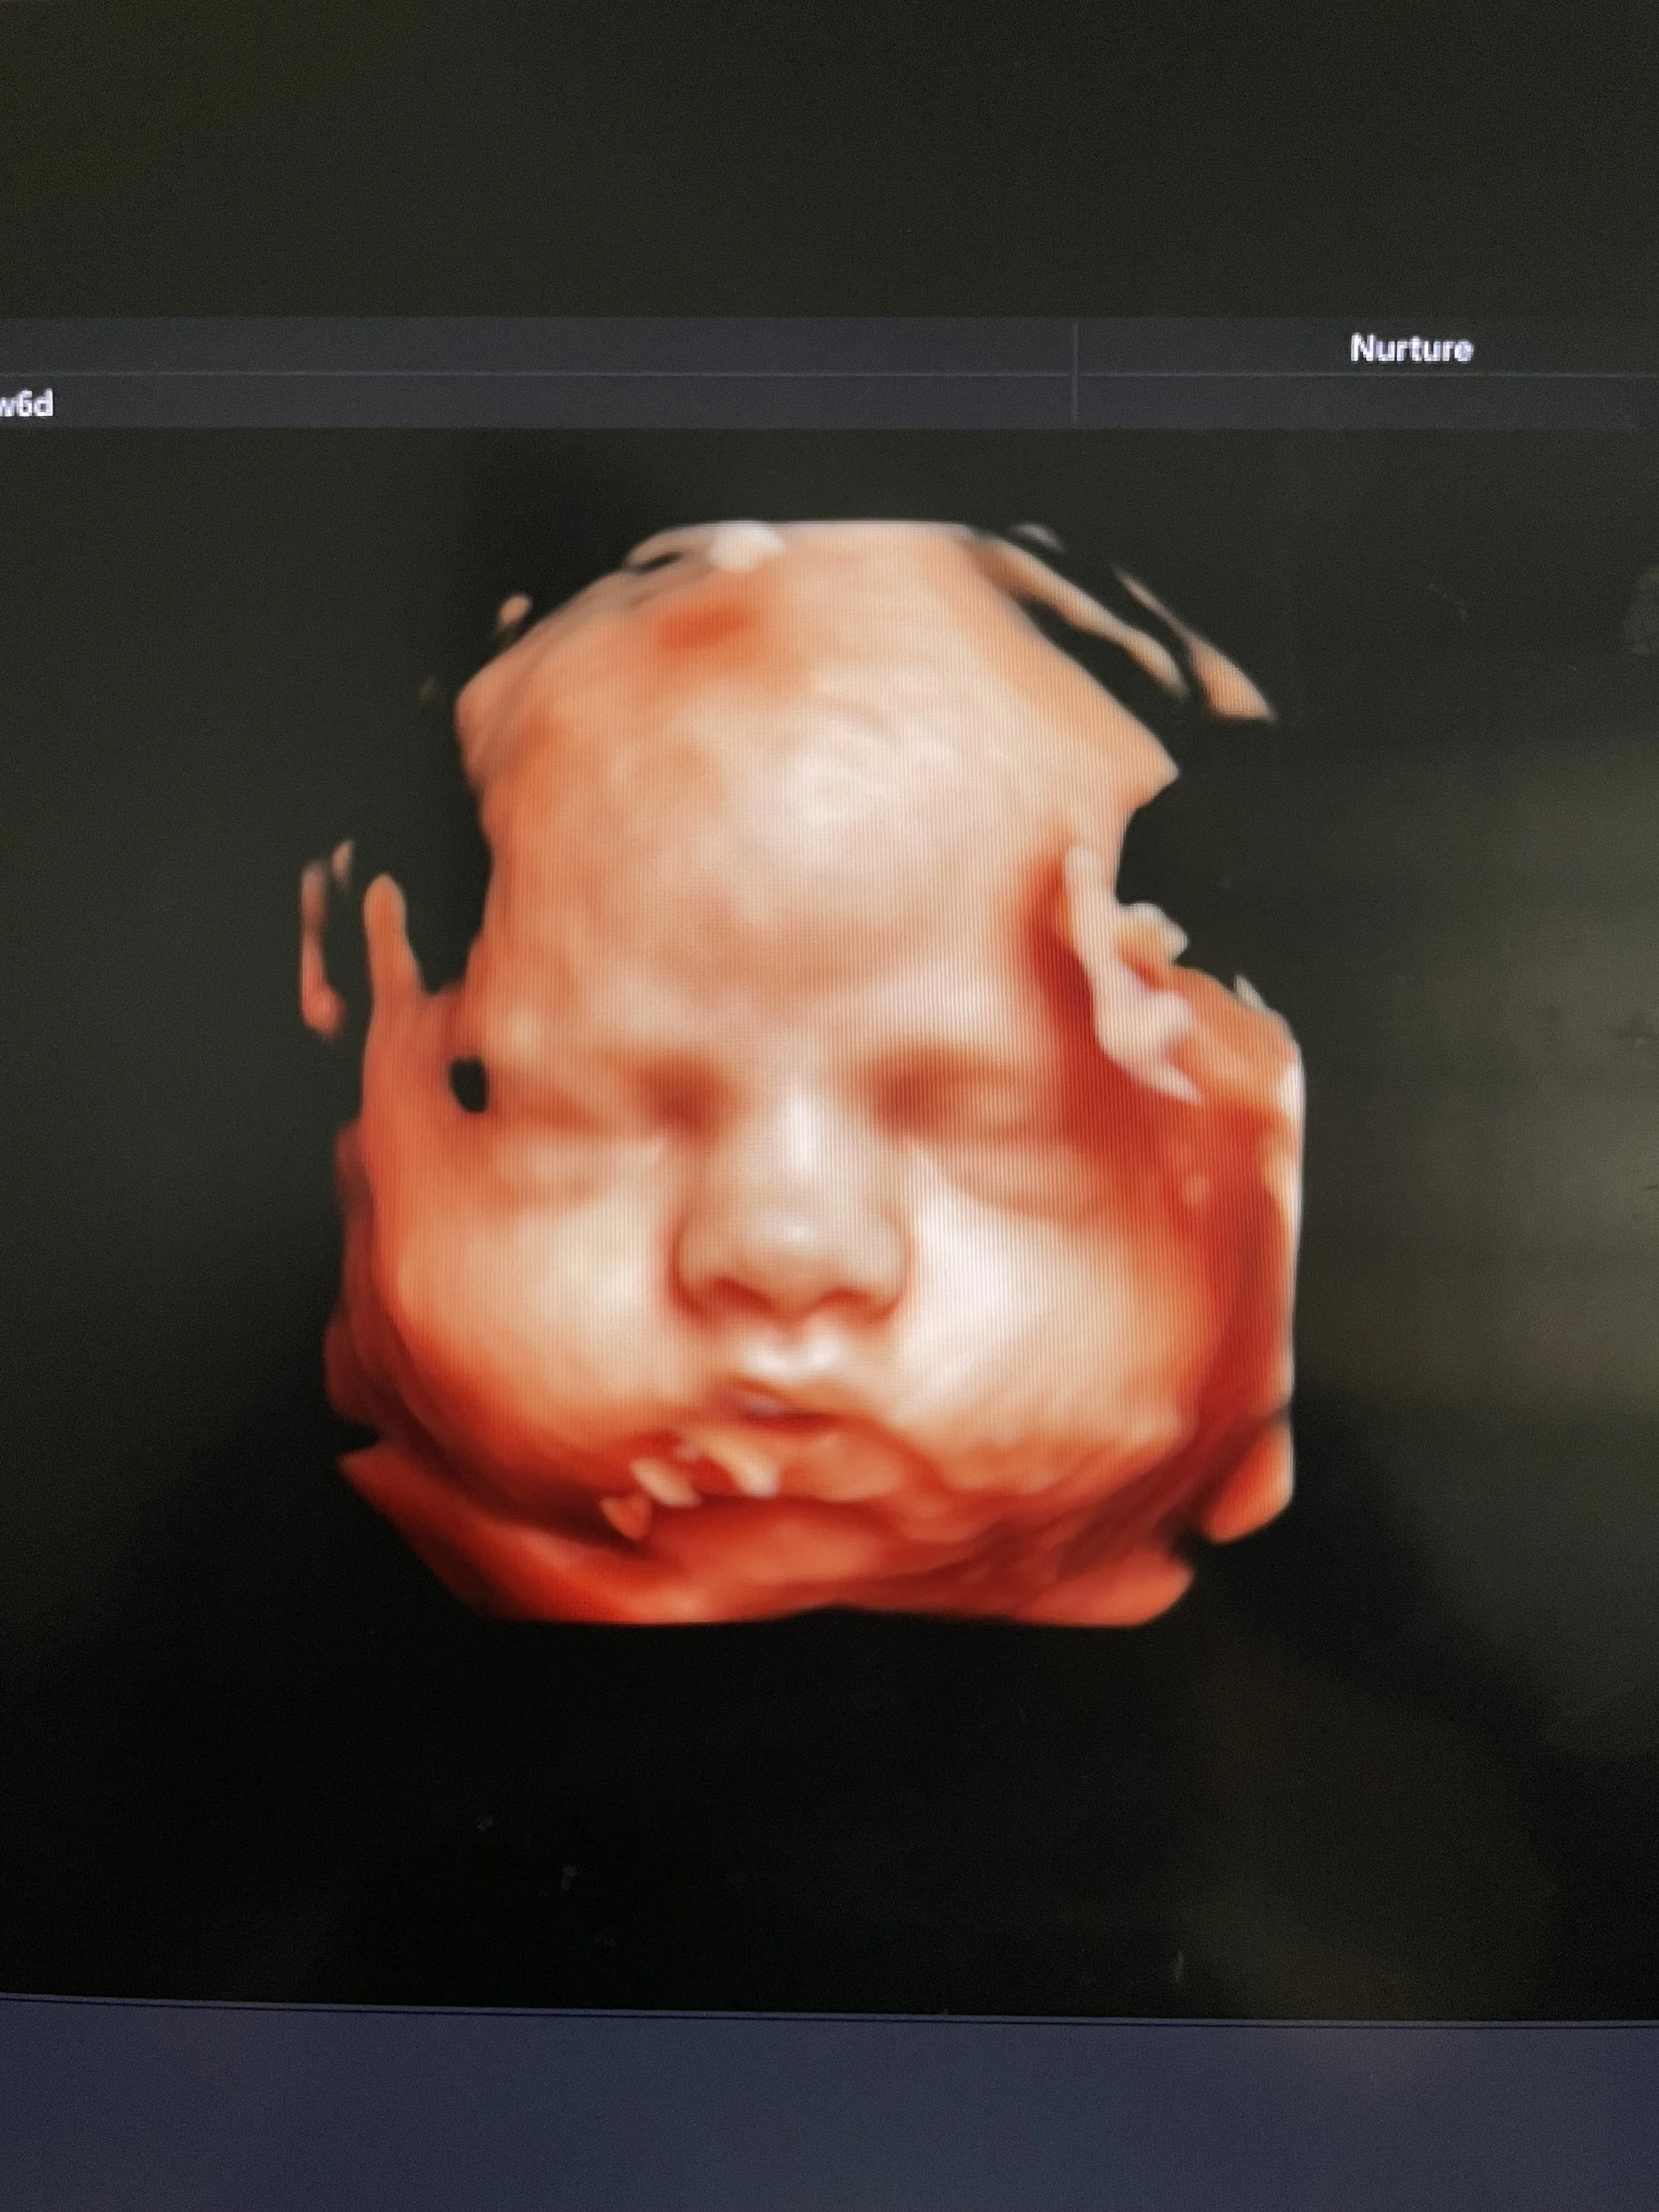

Seeing your baby suck their thumb, purse their little lips together, rub their eyes, and kick their little feet is magical.

Ultrasound image of a fetus inside the womb.

During your session, you’ll watch your baby in real time—seeing their movements, their expressions, their unique rhythms. These are moments of life in utero that are usually unseen, yet deeply felt. Many families describe it as the first time everything becomes real in a new way.